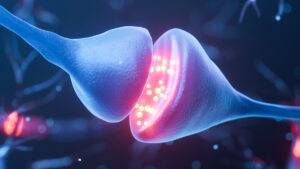

کشف اسرار پارکینسون با تصویربرداری به روش شوک و انجماد

محققان به روش جدید و هوشمندانهای برای منجمد کردن سلولهای مغزی دقیقاً در لحظه شلیک سیگنال دست یافتهاند؛ این بدان معناست که فرآیندهایی که معمولاً با سرعتی فراتر از توان مشاهده رخ میدهند، اکنون با ادامه مطلب